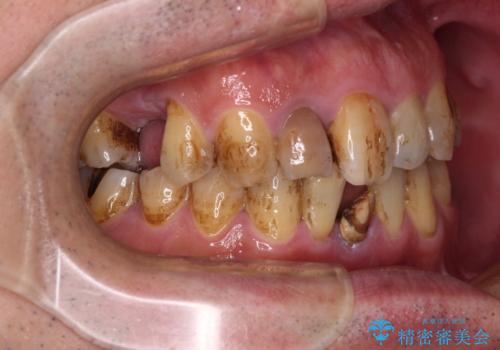

- むし歯治療途中で放置された歯が多く、スペースができたり歯が寄って来たりしているのを気にして来院された患者様です。

矯正治療を行いながら、欠損部はインプラントによる補綴治療を希望されたため、補助装置を用いたワイヤー矯正によりスペースを確保しながら歯列を整え、適宜インプラントを埋入していくこととしました。